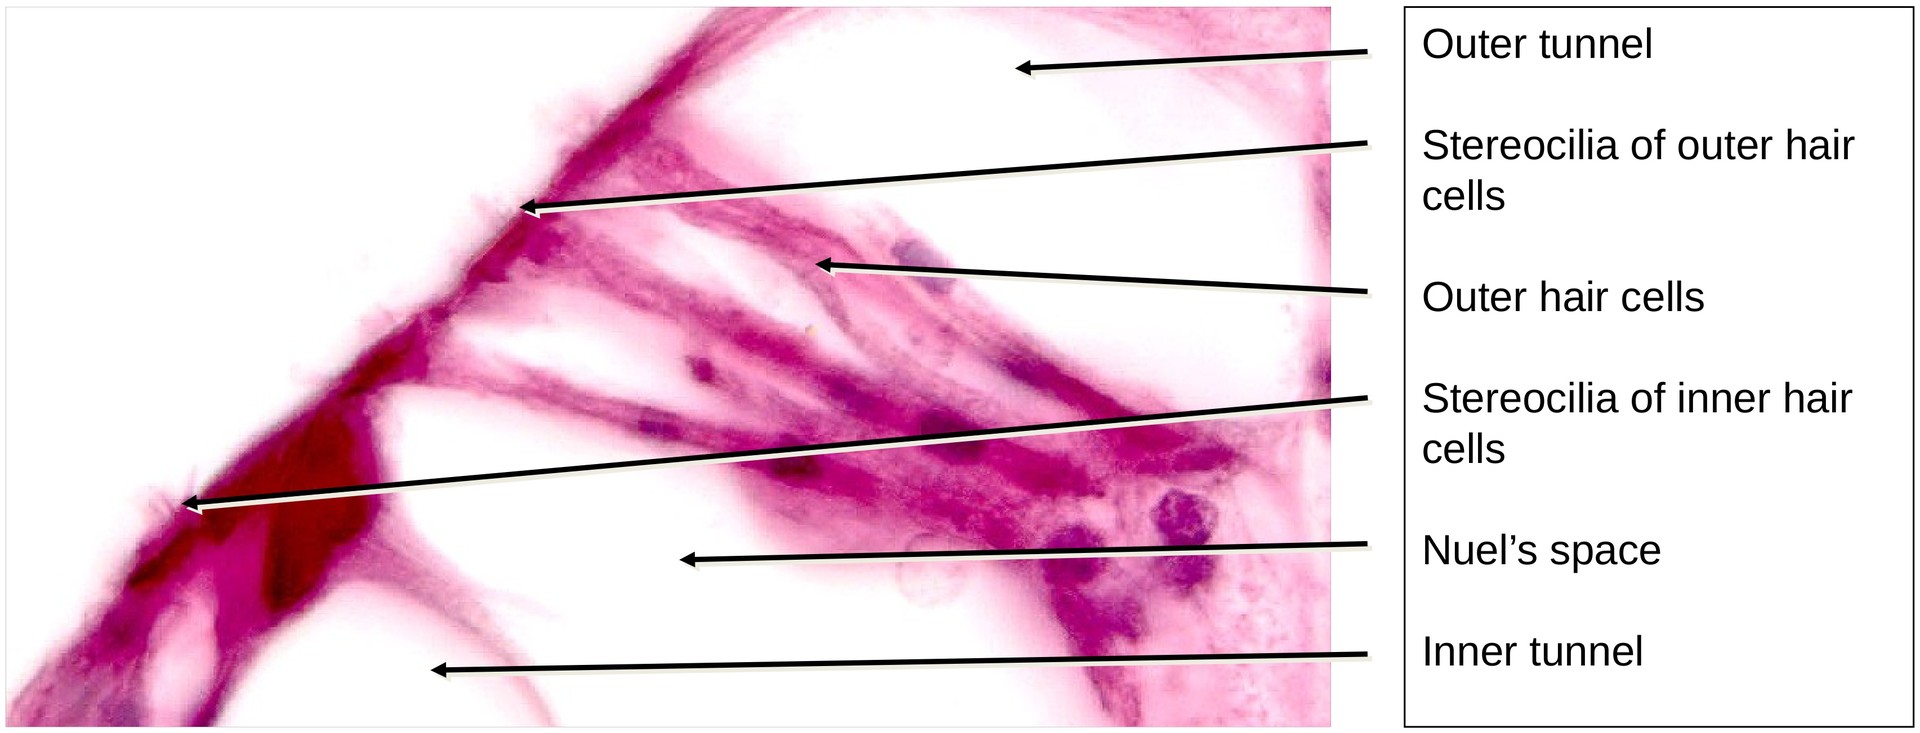

Organ of Corti:

The organ of Corti is the sensory epithelium responsible for sound transduction. It contains:

- Inner hair cells (a single row), and

- Outer hair cells (three to five rows), each covered with stereocilia that normally make contact with the tectorial membrane (membrana tectoria). In this preparation, due to decalcification and fixation, the tectorial membrane has detached from the hair cells.

Supporting cells include:

- Inner and outer phalangeal cells supporting the hair cells,

- Inner and outer pillar cells, which together form the inner tunnel,

- Hensen’s cells and Claudius’ cells, located laterally beyond the outer hair cells, and

- The outer boundary cells forming the external spiral sulcus.

The organ of Corti is traversed by several fluid-filled spaces:

- Inner tunnel, bounded by the inner and outer pillar cells,

- Nuel’s space, between the outer pillar cells and outer hair cells, and

- Outer tunnel, between the outer boundary cells and outer hair cells.